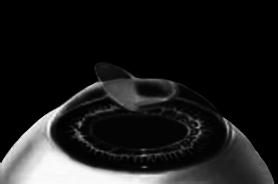

Края роговичного лоскута осушают сухим тупфером. Влага, оставшаяся под лоскутом в ямке роговичного ложа, высасывается в тупфер. Лоскут притягивает к ложу, как вакуумную присоску. Вакуумом начали, вакуумом закончили.

Ждем, когда закончится приживление лоскута к ложу. Эпителий цел и невредим. А значит, никаких болей. Около трех часов возможны слезотечение и светобоязнь. И все (рис. 9).